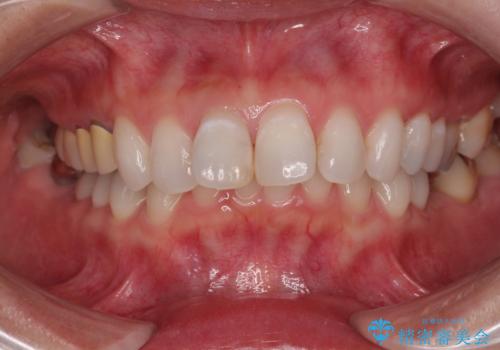

- 前歯の変色と、以前装着したクラウンが黄ばんできたことを気にして来院された患者様です。

前歯に変色が起こる場合、神経組織の失活により引き起こる可能性が高いため、診察を行ったところ、根尖部の病変や叩いたときの痛みなどが認められました。

まずは根管治療を行い、痛みの消退を確認してからオールセラミッククラウンによる補綴治療を行うこととしました。

黄ばんできてしまった小臼歯部のクラウンは、根尖部に症状を認めないため、そのままオールセラミッククラウンによる補綴治療を行うこととしました。

色がやや白いと感じましたが、ご自身でホームホワイトニングをされているそうで、今後周辺の歯を白くしていくとのことでした。

前歯に痛みがあるという実感はなかったそうですが、診察で叩いたときの痛みを感じた際、今までに同様の痛みや違和感を感じたことがあったとのことでした。

初回の根管治療で痛みや違和感は消退したため、その後は速やかに補綴治療を行いました。